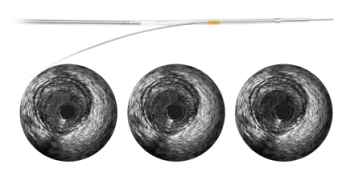

45 MHz-frequency imaging

A 45 MHz frequency produces crisp, sharp imaging for dependable interpretation and assessment of vessel morphology.

3 Hi-Q imaging options

Choose from three high-quality, optimized imaging modes with varying levels of darkness and fineness of blood speckle to assist in differentiating between tissue and blood along the lumen border. High-quality image enhancement is available on all Revolution catheters using Philips Volcano IVUS systems with version 3.3 software and higher. Hi-Q imaging modes are accessible via the “Adjust Image” menu.